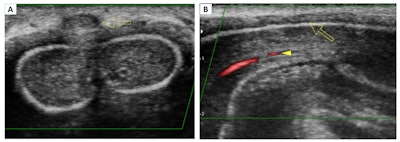

Superficial dorsal vein thrombosis. Color Doppler in transverse (A) and longitudinal (B) planes. The images show an absence of signal from the superficial dorsal vein of the penis and echogenic material related to thrombus (arrow). Presence of flow in the cavernous artery (arrowhead). All figures courtesy of Dr. Iñigo Zubiaguirre Telleria et al and European Society of Radiology (ESR) EPOS database.

Superficial dorsal vein thrombosis, or penile Mondor disease, is a benign and self-limiting process that affects sexually active men, especially during penile erection. It requires a clinical diagnosis (indurated cord on the dorsal aspect of the penis), but ultrasound helps to confirm the diagnosis and enables a follow-up to exclude a possible underlying tumor.

The treatment is conservative -- i.e., sexual rest and nonsteroidal anti-inflammatory medications -- and anticoagulation is not necessary, they noted.

Ultrasound findings include absence of flow and compressibility of the superficial dorsal vein of the penis. "It is possible to identify echogenic material within the vein that confirms the thrombus. In some cases, an increase in the caliber of the vein and inflammation of the adjacent soft tissues are observed," Telleria and colleagues stated.